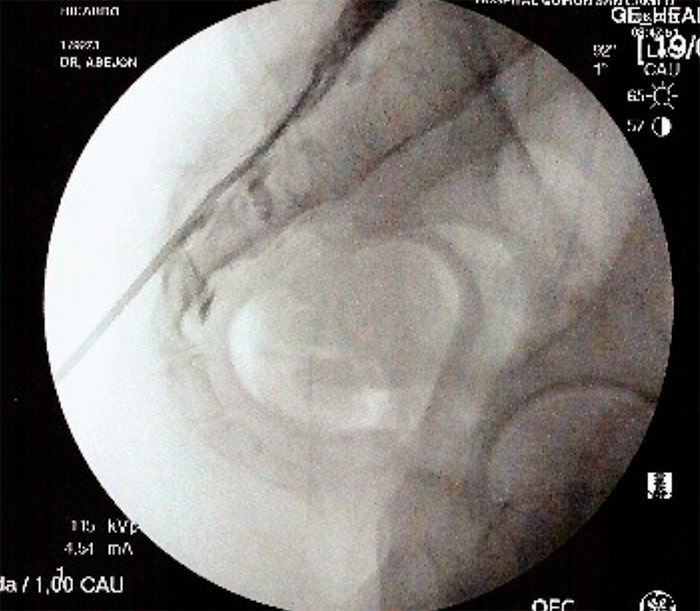

Con el paciente en decúbito prono, se coloca una almohada a la altura de la pelvis para corregir la lordosis fisiológica, y el arco de fluoroscopia en posición AP , con el  marcador radiopaco se localiza la línea media, se gira el arco de fluoroscopia a posición lateral para localizar el hiato sacro. Una vez localizado se infiltra con anestesia local de la piel, tejido celular subcutáneo, ligamento sacrocoxigeo y periostio, y se realiza punción con una aguja introductora con visión continúa hasta atravesar el ligamento sacrocoxigeo, se  administra contraste radiopaco (2-5ml) en visión continua y se comprueba su distribución. Posteriormente se vuelve a comprobar la distribución del contraste con el arco de fluoroscopia en posición anteroposterior (epidurografía). La epidurografía nos permitirá identificar las raíces que no se rellenan con contraste (fibrosis).

A continuación se introduce un catéter y se dirige hacia la zona de amputación radiológica, en el espacio epidural anterior. Con el arco de rayos en posición lateral, se inyectan 10ml de suero salino 0.9% con 1500v de hialuronidasa en la zona de amputación, posteriormente se inyecta de 3-5ml de contraste radiológico para visualizar la apertura del espacio, y a continuación se inyecta 9ml de Bupivacaina 0.25% y 40mg de triamcinolona. Se retira la aguja introductora y el catéter y se coloca un apósito. Hay autores que dejan el catéter durante 3 días y vuelven a inyectar el anestésico local y suero salino fisiológico al 10% (está en discusión). Con el catéter de RCE Cosman, se dirige a la zona amputada de contraste, se sigue el procedimiento anterior y además se intenta dirigir la punta del catéter debajo del pedículo que es donde se encontraría el ganglio de la raíz dorsal y se procede a hacer radiofrecuencia pulsada (estimulo sensitivo alrededor de 0.5v y el 45v, por un periodo de 2 a 8 minutos.